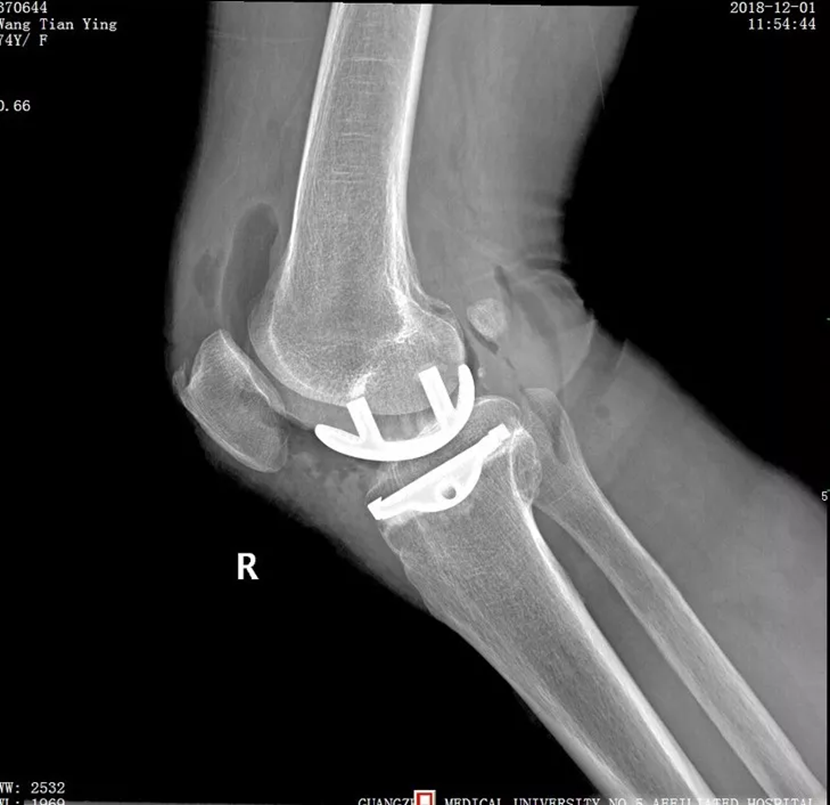

陈为坚主任对患者进行了仔细检查,发现她的左膝关节内翻畸形,也就是百姓常说的“罗圈腿”,一按压关节内侧就明显疼痛。X 光片、核磁共振报告左膝关节内侧软骨明显磨损,关节间隙明显变窄,被诊断为骨性关节炎。像这样的病情,以往一般会采取全膝关节置换手术治疗,但这需要对整个膝关节的关节面进行截骨,切除过多正常的骨质、交叉韧带和外侧半月板,损伤比较大。

陈为坚主任仔细研究患者的实际病情,最终制定了微创下膝关节单髁置换的手术方案。随后,陈为坚主任为患者实施手术,术中切除膝关节内侧已经磨损和破坏的软骨表面,用人工假体进行置换,用骨水泥进行固定。仅仅两个小时,手术就顺利完成。术后第二天王阿姨即可下地行走,疼痛大大减轻。“真是感谢医生,我这一下算是脱胎换骨了。”王阿姨说。

膝关节单髁置换是相对全膝关节置换而言的一种新型微创手术,简单讲就是“哪里坏了换哪里”。陈为坚主任介绍,人体的膝关节包含内侧胫股间室、外侧胫股间室、髌股间室3个间室。如果3个间室都有不同程度的磨损,疼痛影响了日常生活就需要行全膝关节置换。传统的膝关节置换,是对全膝关节的整体置换。如果只有1个间室磨损较大,其他两个间室良好,那么,膝关节单髁置换术就是这类患者的有效手段,通过微创化、精准化的手术操作,仅对单一磨损严重的间室进行更换,在磨损的关节面上加上“保护套”,不影响其他间室的正常功能。

“单髁置换的创伤要比全膝置换小很多,术中仅切除损毁的软骨和少量的软骨下骨,只作‘表面’置换,不碰及外侧,又完整地保留了交叉韧带、副韧带,术后恢复快,同时,住院时间也明显降低,极大地方便了患者。”